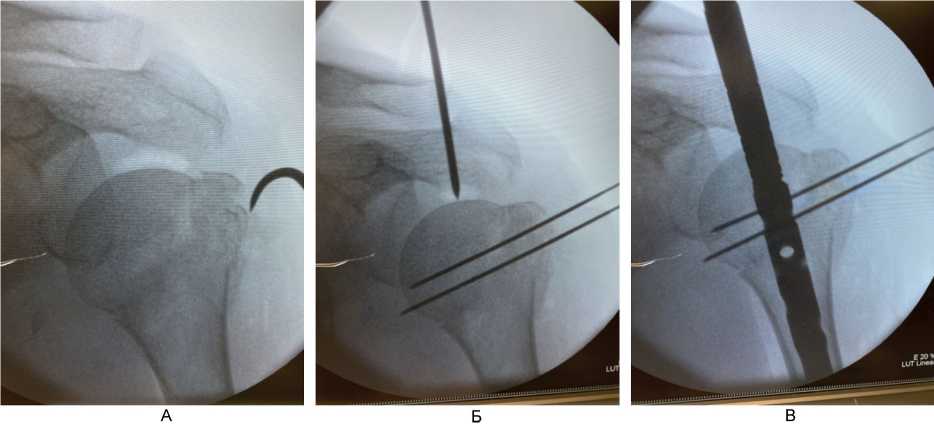

При переломах типа В по АО с выраженным смещением большого бугорка плечевой кости использовали минимально инвазивную методику остеосинтеза. Выполняли доступ по наружной поверхности в области плечевого сустава длиной 3–4 см в проекции большого бугорка, с помощью однозубого крючка производили репозицию большого бугорка и временную фиксацию его 2 спицами Киршнера (рис. 5). Спицы вводили таким образом, чтобы в ходе операции предотвратить возможные конфликты в процессе вскрытия, рассверливания костномозгового канала и введения штифта. После введения штифта большой бугорок фиксировали блокирующим винтом (дополнительно по необходимости применяли методику «винт в винте» [21]), при оскольчатом переломе большого бугорка для более надежной фиксации мелкого фрагмента дополнительно подшивали его через специальное отверстие в блокирующем винте, далее спицы удаляли. Блокирующие винты вводили по направителям из проколов длиной 1 см. Интраоперационная кровопотеря составляла не более 50 мл.

Рис. 5. Этапы репозиции отломков и установки интрамедуллярного штифта при переломах типа Б по АО. А – прошивание сухожилий манжеты ротаторов с костными отломками; Б – репозиция и временная фиксация отломков тонкими спицами Киршнера, установка направляющего устройства для вскрытия интрамедуллярного канала плечевой кости; В – установка интрамедуллярного штифта в плечевую кость